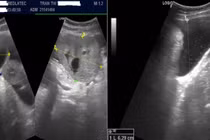

Sau khi kiểm tra, kết hợp chụp MRI vùng chậu và siêu âm tử cung – phần phụ, các bác sĩ phát hiện khối u buồng trứng thuộc nhóm O-RADS 4–5 (nguy cơ ác tính cao). Ngay sau đó, chị được chuyển đến Khoa Ung bướu để tiếp tục điều trị.

Tại đây, các bác sĩ tiến hành hội chẩn và thực hiện nội soi ổ bụng, lấy mẫu sinh thiết. Chỉ sau 20 phút, kết quả xác định: U tế bào hạt buồng trứng phải.